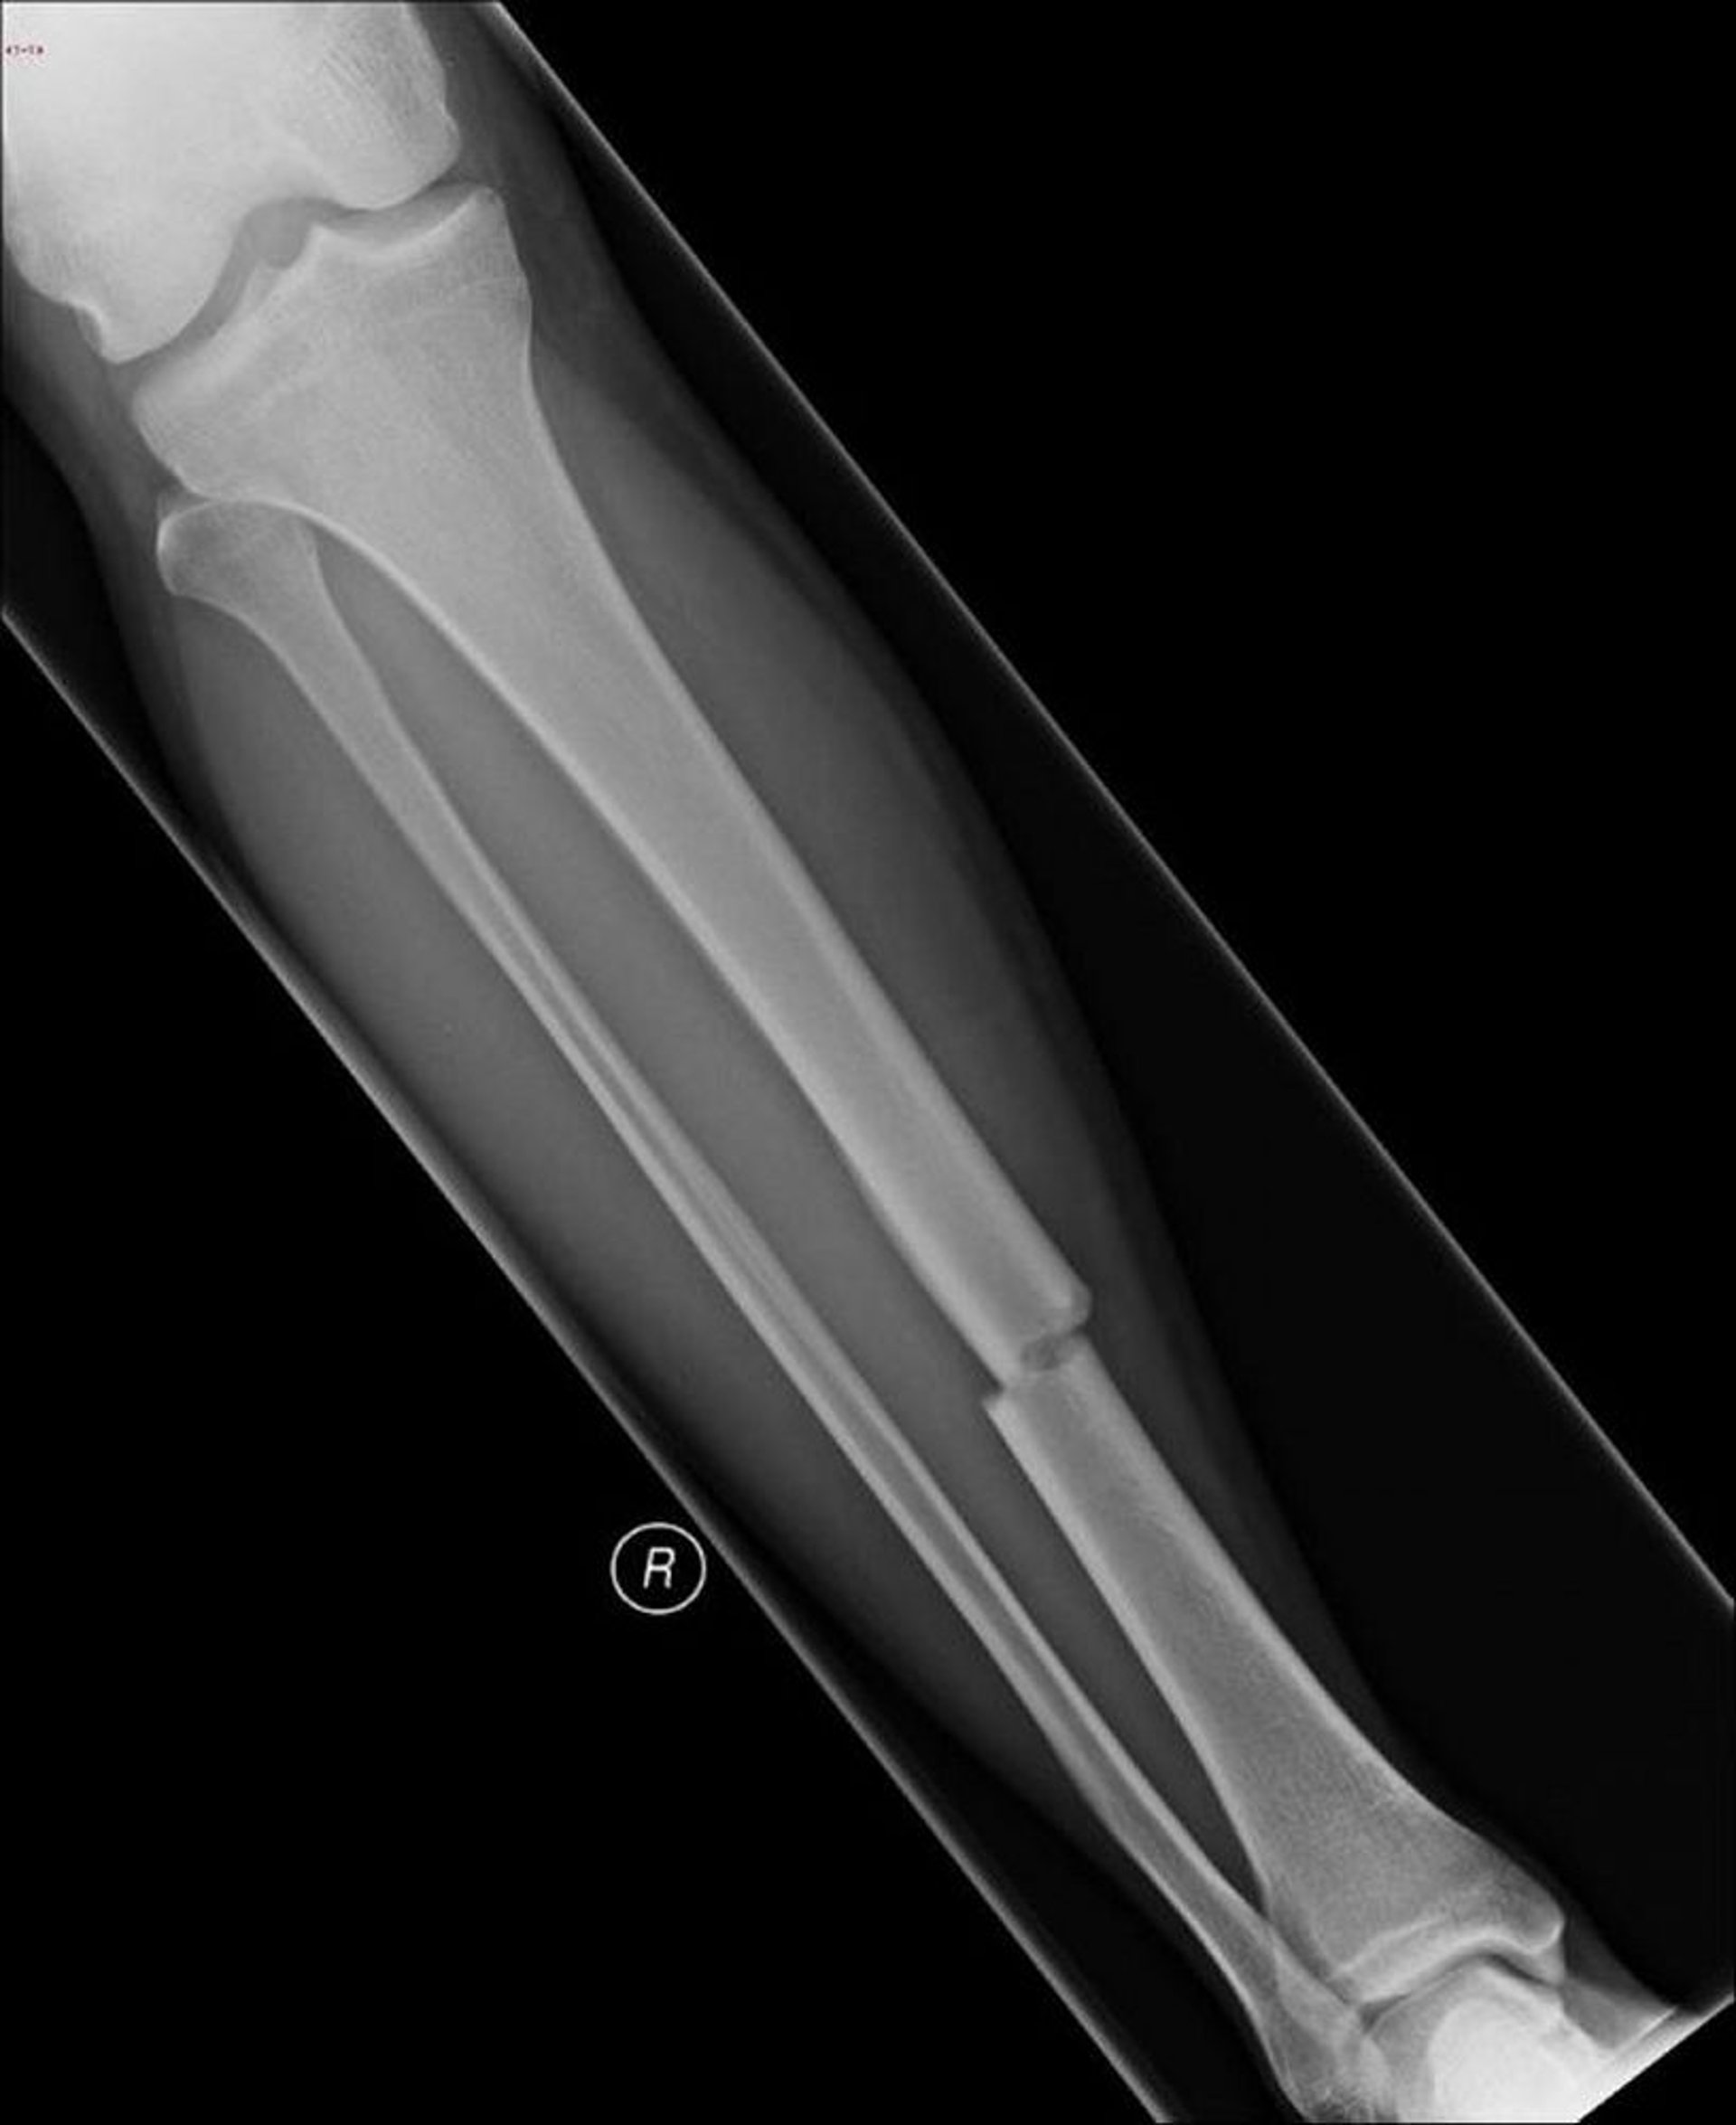

Frattura trasversale della diafisi della tibia

Questa frattura trasversale colpisce la parte mediale della diafisi della tibia.

Image courtesy of Danielle Campagne, MD.